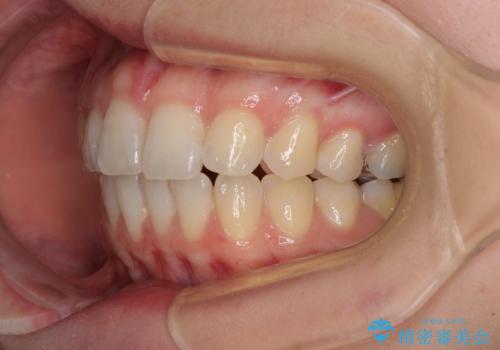

気になる上の歯を改善 インビザライン矯正

- 矯正治療の後戻りが気になるとのことで来院された患者様です。

上顎の後戻りをインビザライン・ライトで治療することとしました。

上顎のみの治療を希望されたため、咬み合わせをしっかりと改善することはできませんでしたが、審美面が大きく改善され、日常生活の機能面でも不具合を感じることはなく、大変満足していただきました。